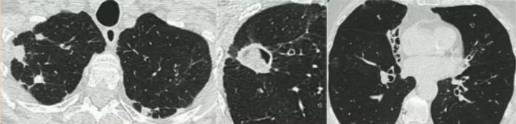

慢性空洞性肺曲霉病(CCPA):最常见,单发或多发的肺空洞(薄壁或厚壁),空洞内可包含一个或多个曲菌球或不规则的腔内物质,具有曲霉菌血清学和微生物学依据,并有明显肺部和全身症状,至少3个多月的观察有放射影像学进展(新发空洞,空洞外周浸润增加及纤维增生增加)。

曲霉结节:不常见,单发或多个结节(<3cm),有或没有空洞,常出现坏死,但不表现为组织侵袭。易与结核、肺癌、肺球孢子菌及其他疾病混淆,只能依靠组织学明确诊断。

亚急性侵袭性肺曲霉病(SAIA):轻度免疫缺陷的侵袭性肺曲霉病患者,发生在1-3个月内,具有可变的影像学特征,包括空洞、结节、有“脓肿形成的进展性实变”。最重要的特征为肺组织发现菌丝,另血液或呼吸液GM试验呈强阳性。